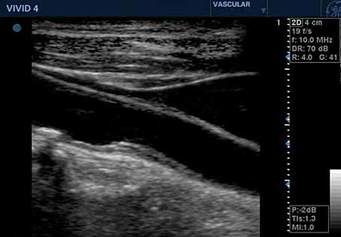

Um das Risiko für einen Schlaganfall besser einschätzen zu können, sind folgende Untersuchungen sinnvoll bzw. hilfreich: